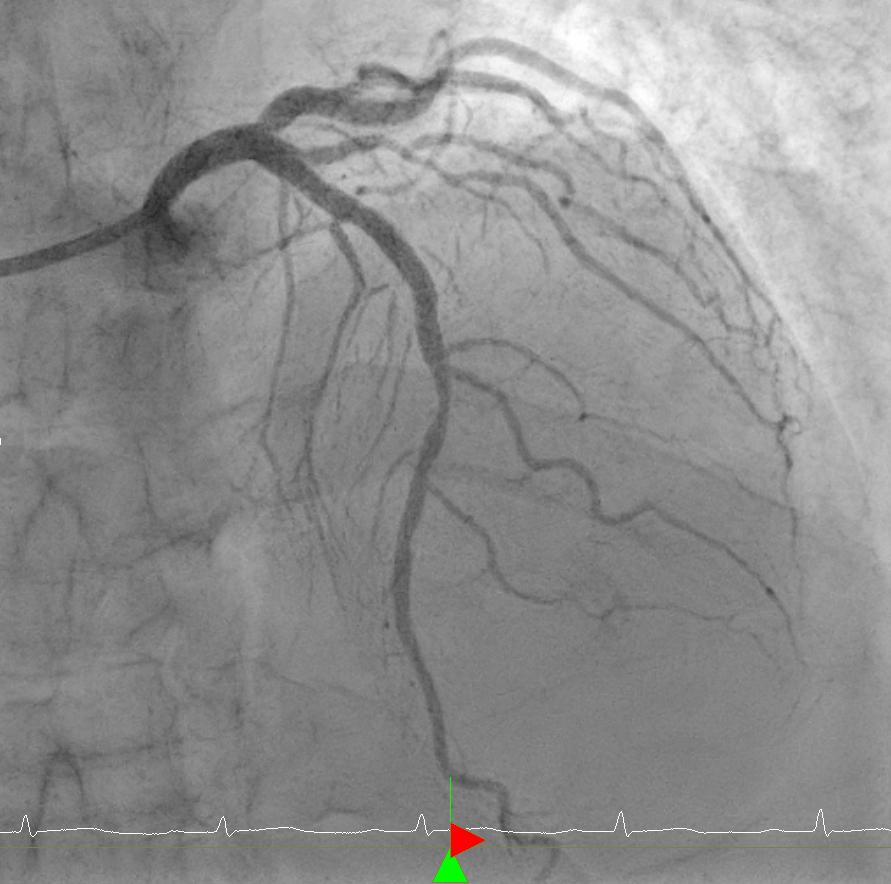

관동맥(관상동맥) 조영술이란, 심장에 위치한 심장을 먹여 살리는 혈관인 관상동맥의 상태를 확인하기 위해 시행하는 검사로 심도자술에서 사용한 카테터를 이용하여 심장 관상동맥 안쪽으로 조금씩 조영제를 써가며 그림자를 확인하는 방법이다.

영어로는 Coronary angiography라고 하는데, 조영제가 충전된 혈관의 그림자 모양을 본다는 의미에서 angiography(혈관조영술)라는 용어를 사용한다.

실제 관상동맥 조영술 중 촬영한 영상으로, 가늘고 기다란 카테터를 진입하여 심장의 관상동맥을 확인하고 좁아지거나 막힌 부분을 찾게 된다.

이후 막혀있는 혈과는 뚫어주고, 좁아진 혈관은 넓혀주는 시술(ballooning)을 진행하게 된다. 그리고 이후 넓혀진 혈관의 내벽이 잘 유지되도록 스텐트(stent)를 삽입하게 된다. 스텐트는 그물모양의 금속을 뜻하며 스텐트를 설치하는 시술을 stenting이라고 한다. Ballooning과 stenting 등 조영술을 하면서 치료적 개념으로 하는 시술을 관상동맥중재술(PCI, percutaneous coronary intervention)이라고 한다.